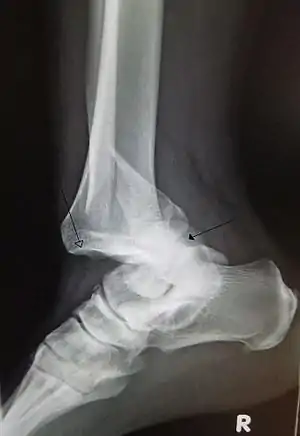

| تال مفصل تیبیوتالار مچ پا همراه شکستگی در فیبولا (نازکنی) دیستال. فلش سفید نشان دهنده تیبیا (درشتنی) و فلش توپر نشانه استخوان شیب. | |